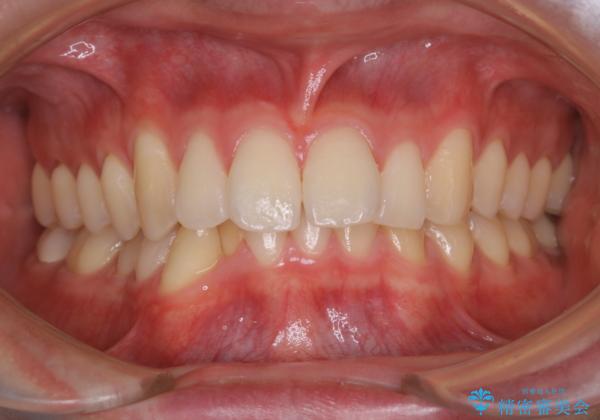

- 口元の突出感は気にならないが、上の前歯の角度と、下の前歯のがたつきが気になるとご相談にいらした方です。なるべく費用や治療期間を抑えて治療したいとのご希望に合わせて治療を計画しました。

この患者様への治療方針として、奥歯から少しずつ歯を移動させる方法と、歯をわずかに削って並べる方法とをご提案しました。短期間での治療を望まれたため、歯をサイズダウンさせて歯を並べました。わずかではあるものの、削った歯は元には戻せないことを十分ご説明し、ご理解ご了承を頂いた上で治療を行いました。